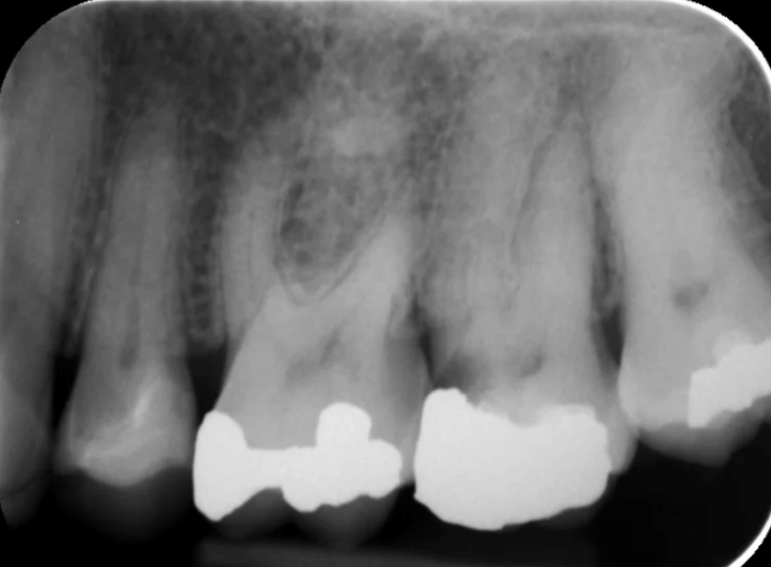

Root filling of a molar tooth.